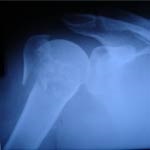

در سال 1363 در رشته پزشکی دردانشگاه تهران پذیرفته شده و در سال 1370 فارغ تحصیل شدم . پس از گذراندن خدمت سربازی و طرح ، دوره رزیدنتی رشته ارتوپدی را در دانشگاه ایران شروع و در 1378 بعنوان متخصص رشته ارتوپدی (جراحی استخوان و مفاصل) شروع به کار کردم. با ادامه همکاری با اساتید این رشته در زمینه تروما بخصوص موارد مشکل شکستگی های داخل مفصلی و شکستگی های لگن تجربیات گرانقدری کسب کردم و در حال حاضر بعنوان عضو انجمن بین المللی تروما (Faculty of AO) هستم . بعلت علاقه به جراحی آرتروسکوپی شانه و زانو در سال 1384 بمدت 6 ماه در کشور اتریش دوره تکمیلی در زمینه جراحی ورزشی (Arthroscopy & Sport Traumatology) را طی کرده و در سال 1386 بمدت 15 ماه دوره فلوشیپ (فوق تخصصی) جراحی شانه و آرتروسکوپی را تحت نظر پروفسور فانک در کشور انگلستان گذراندم. جراحی های بسته (آرتروسکوپیک ) مفاصل در سالهای اخیر بسیار متداول شده اند و بعلت نتیجه خوب و بهبودی سریعتر بیماران نسبت به عمل های باز بسیار مورد توجه قرار گرفته اند. پیشرفت تکنولوژی و مهارت جراحان در این زمینه فوق العاده است و کمک بالایی به بیماران نموده است. من با توجه به گذراندن دوره فلوشیپ در این زمینه سعی کرده ام مهارتم در خدمت بیماران باشد و در حال حاضر علاوه بر ویزیت بیماران در مطب بعنوان جراح شانه با بیمارستان کسری همکاری دارم.